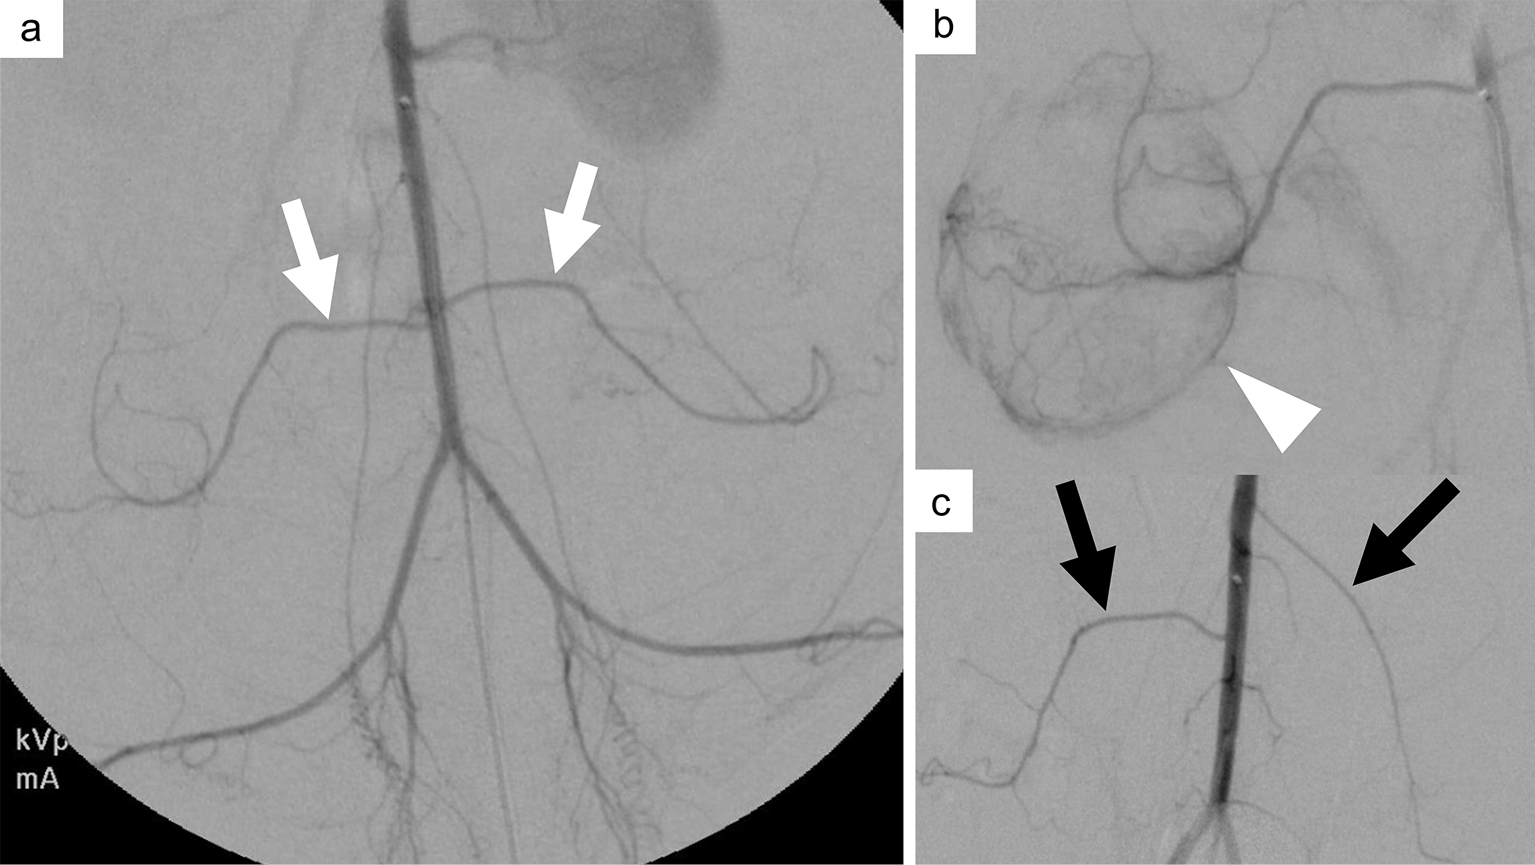

- 3A Review of Treatment for Type II Endoleak after Endovascular Abdominal Aortic Aneurysm RepairHiroki Horinouchi